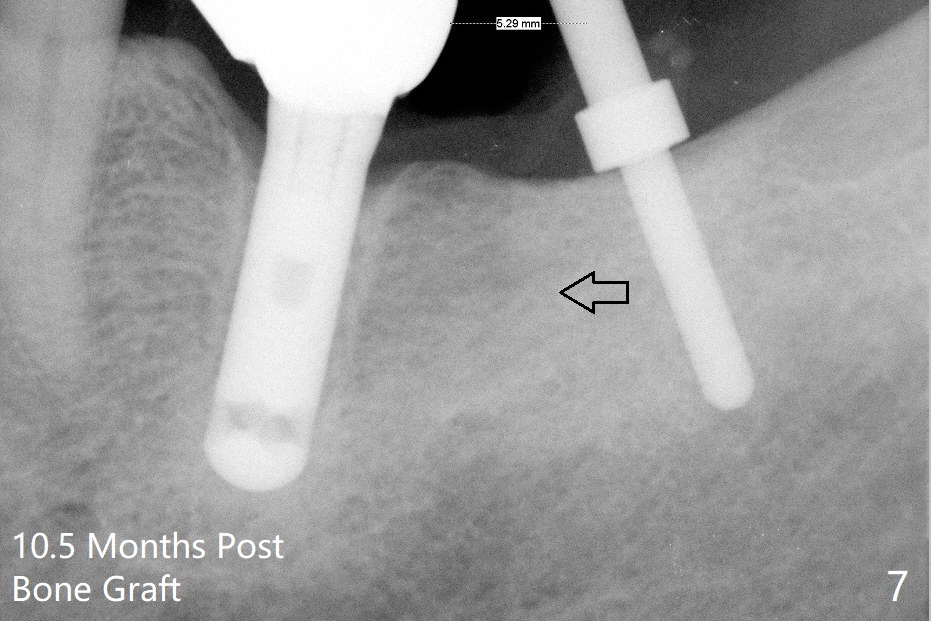

A 69-year-old man needs an implant at #18 (Fig.1,2 CT (sagittal and coronal sections)). In spite of use of surgical stent, the trajectory is not ideal (Fig.3-5). The following day the implant is removed with bone graft (Fig.6). In the 2nd placement, the trajectory is adjusted in each step (Fig.7-9 arrows) with long term stability (Fig.10,11).